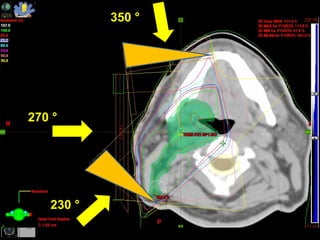

350 ° 270 ° 230 °

350 ° 270° 230 °